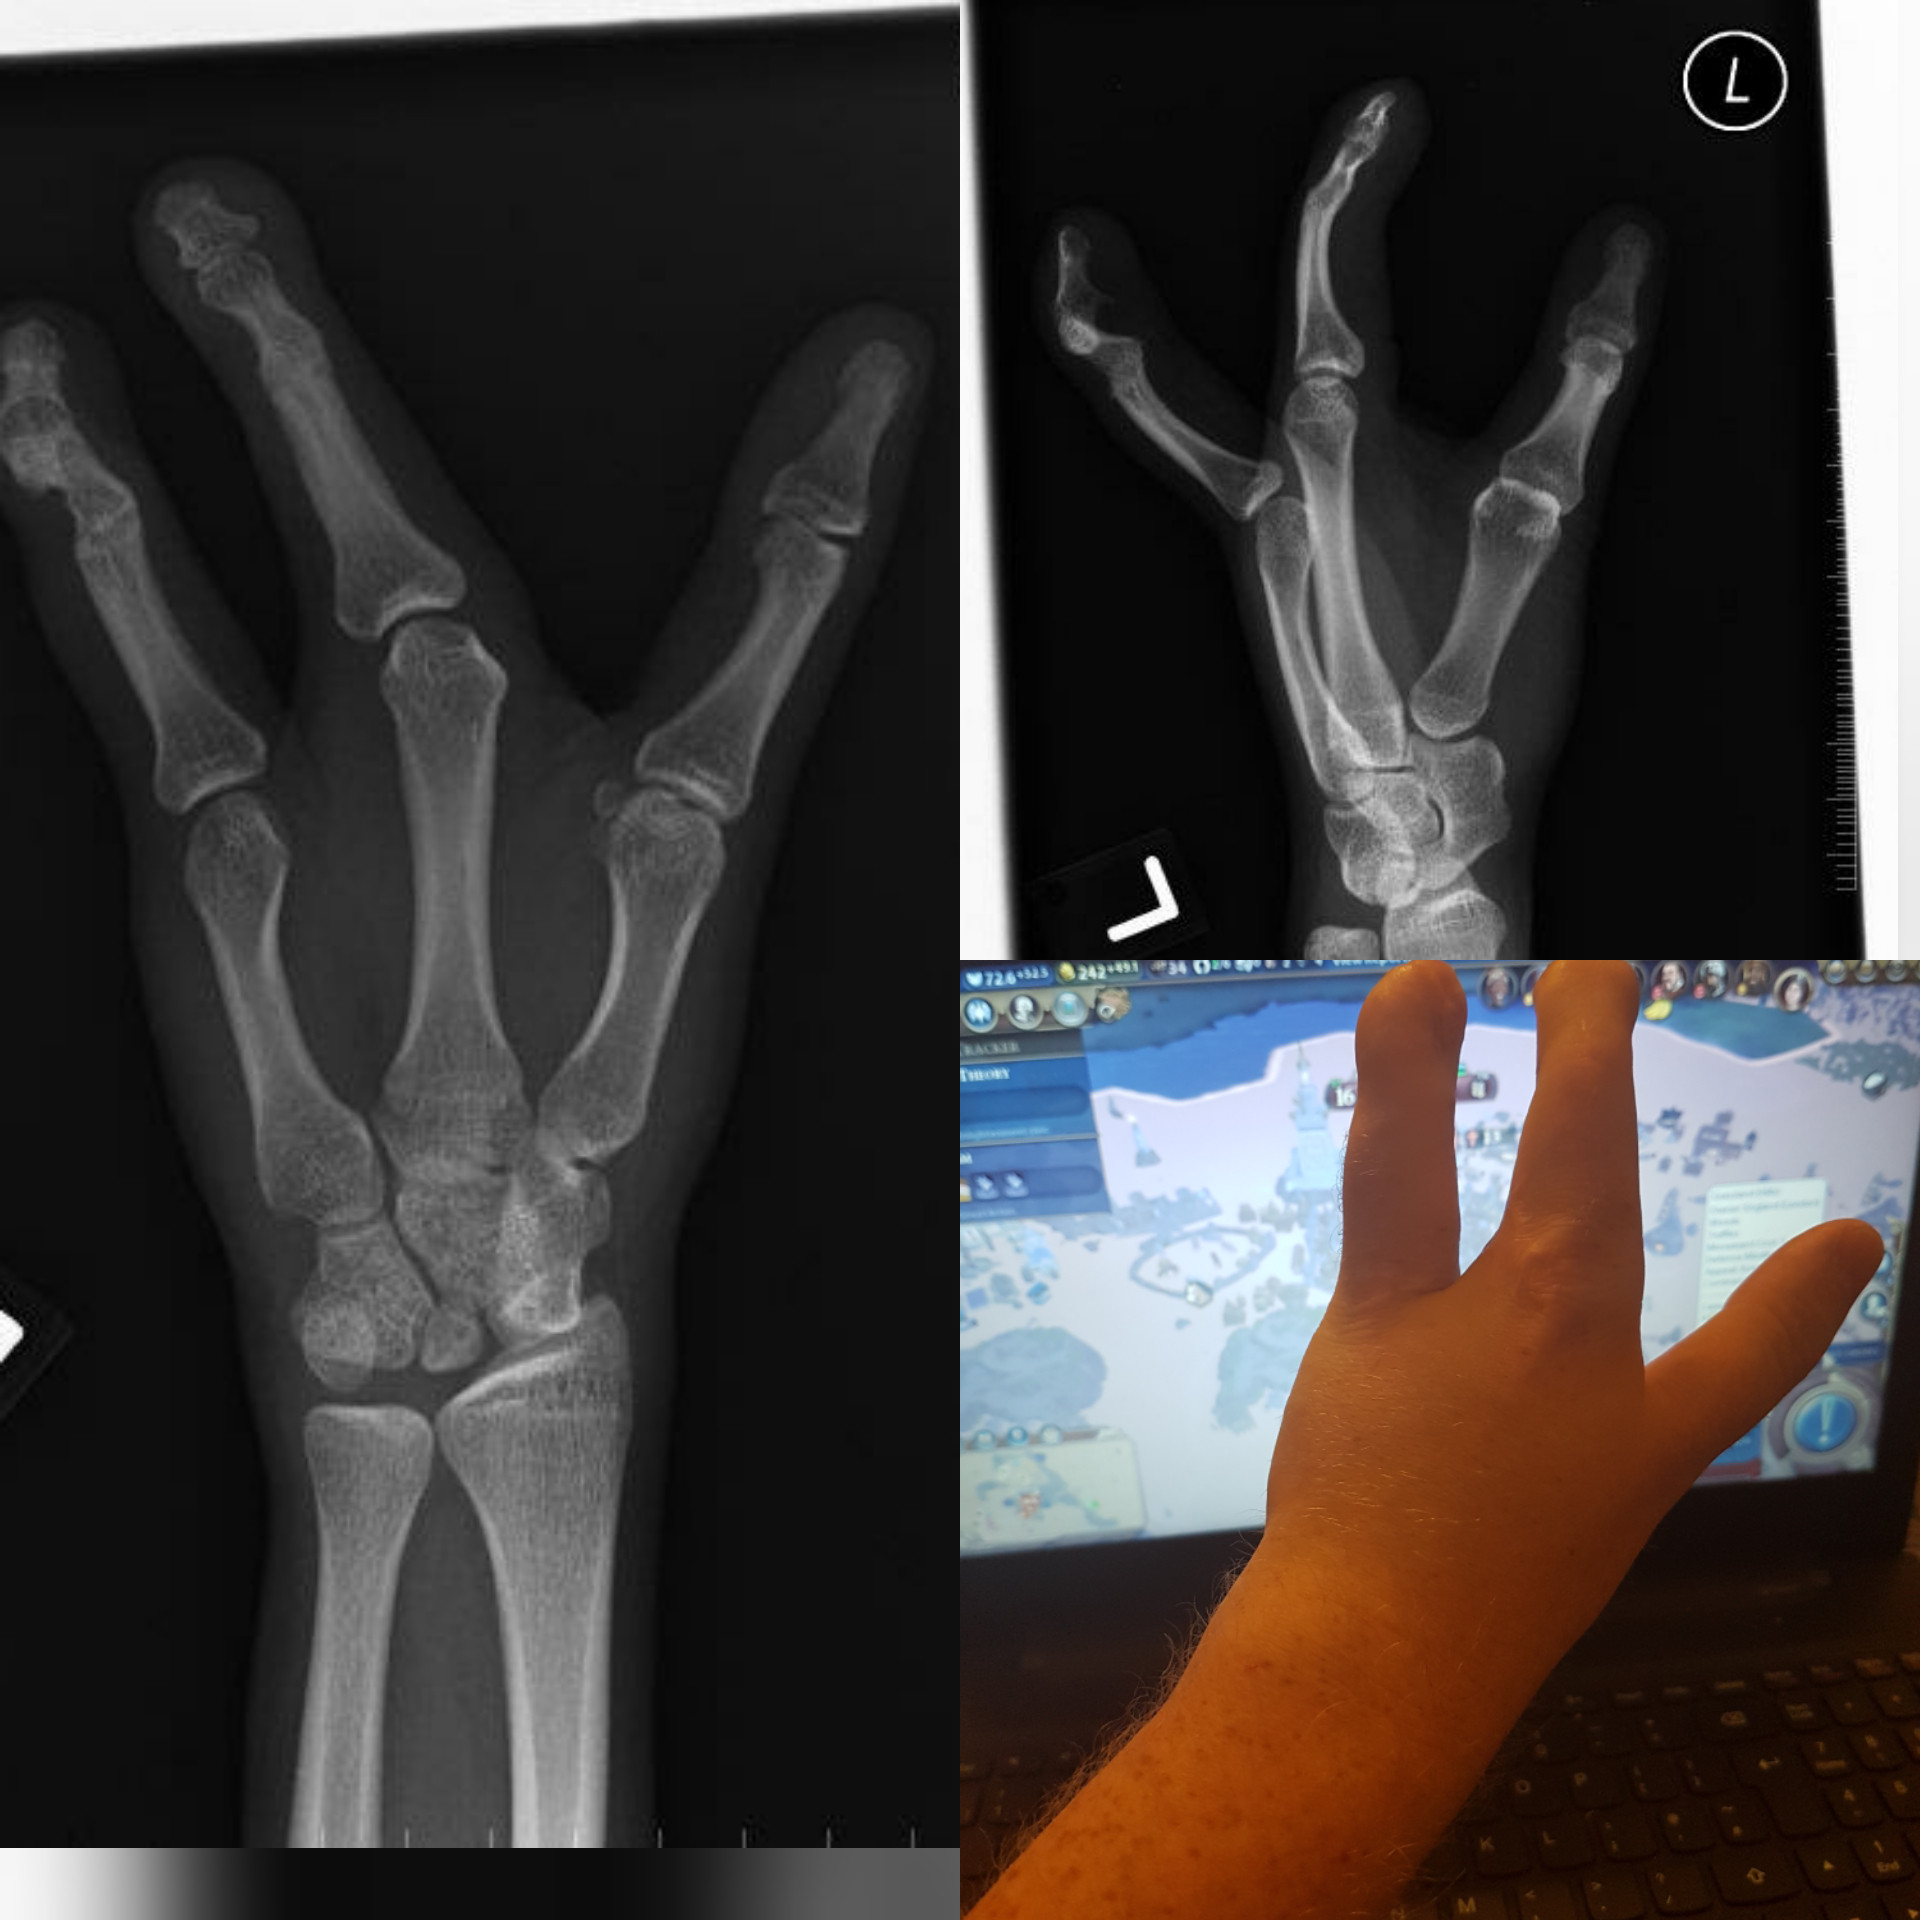

différente des autres cette main est

Tauren IRL

Quand tes parents ont joué à Spore IRL

Trop bien, une tortue ninja !

Ce n'est pas une «main courante»

1..2..3.. soleil !

Quand le cosplay va trop loin...